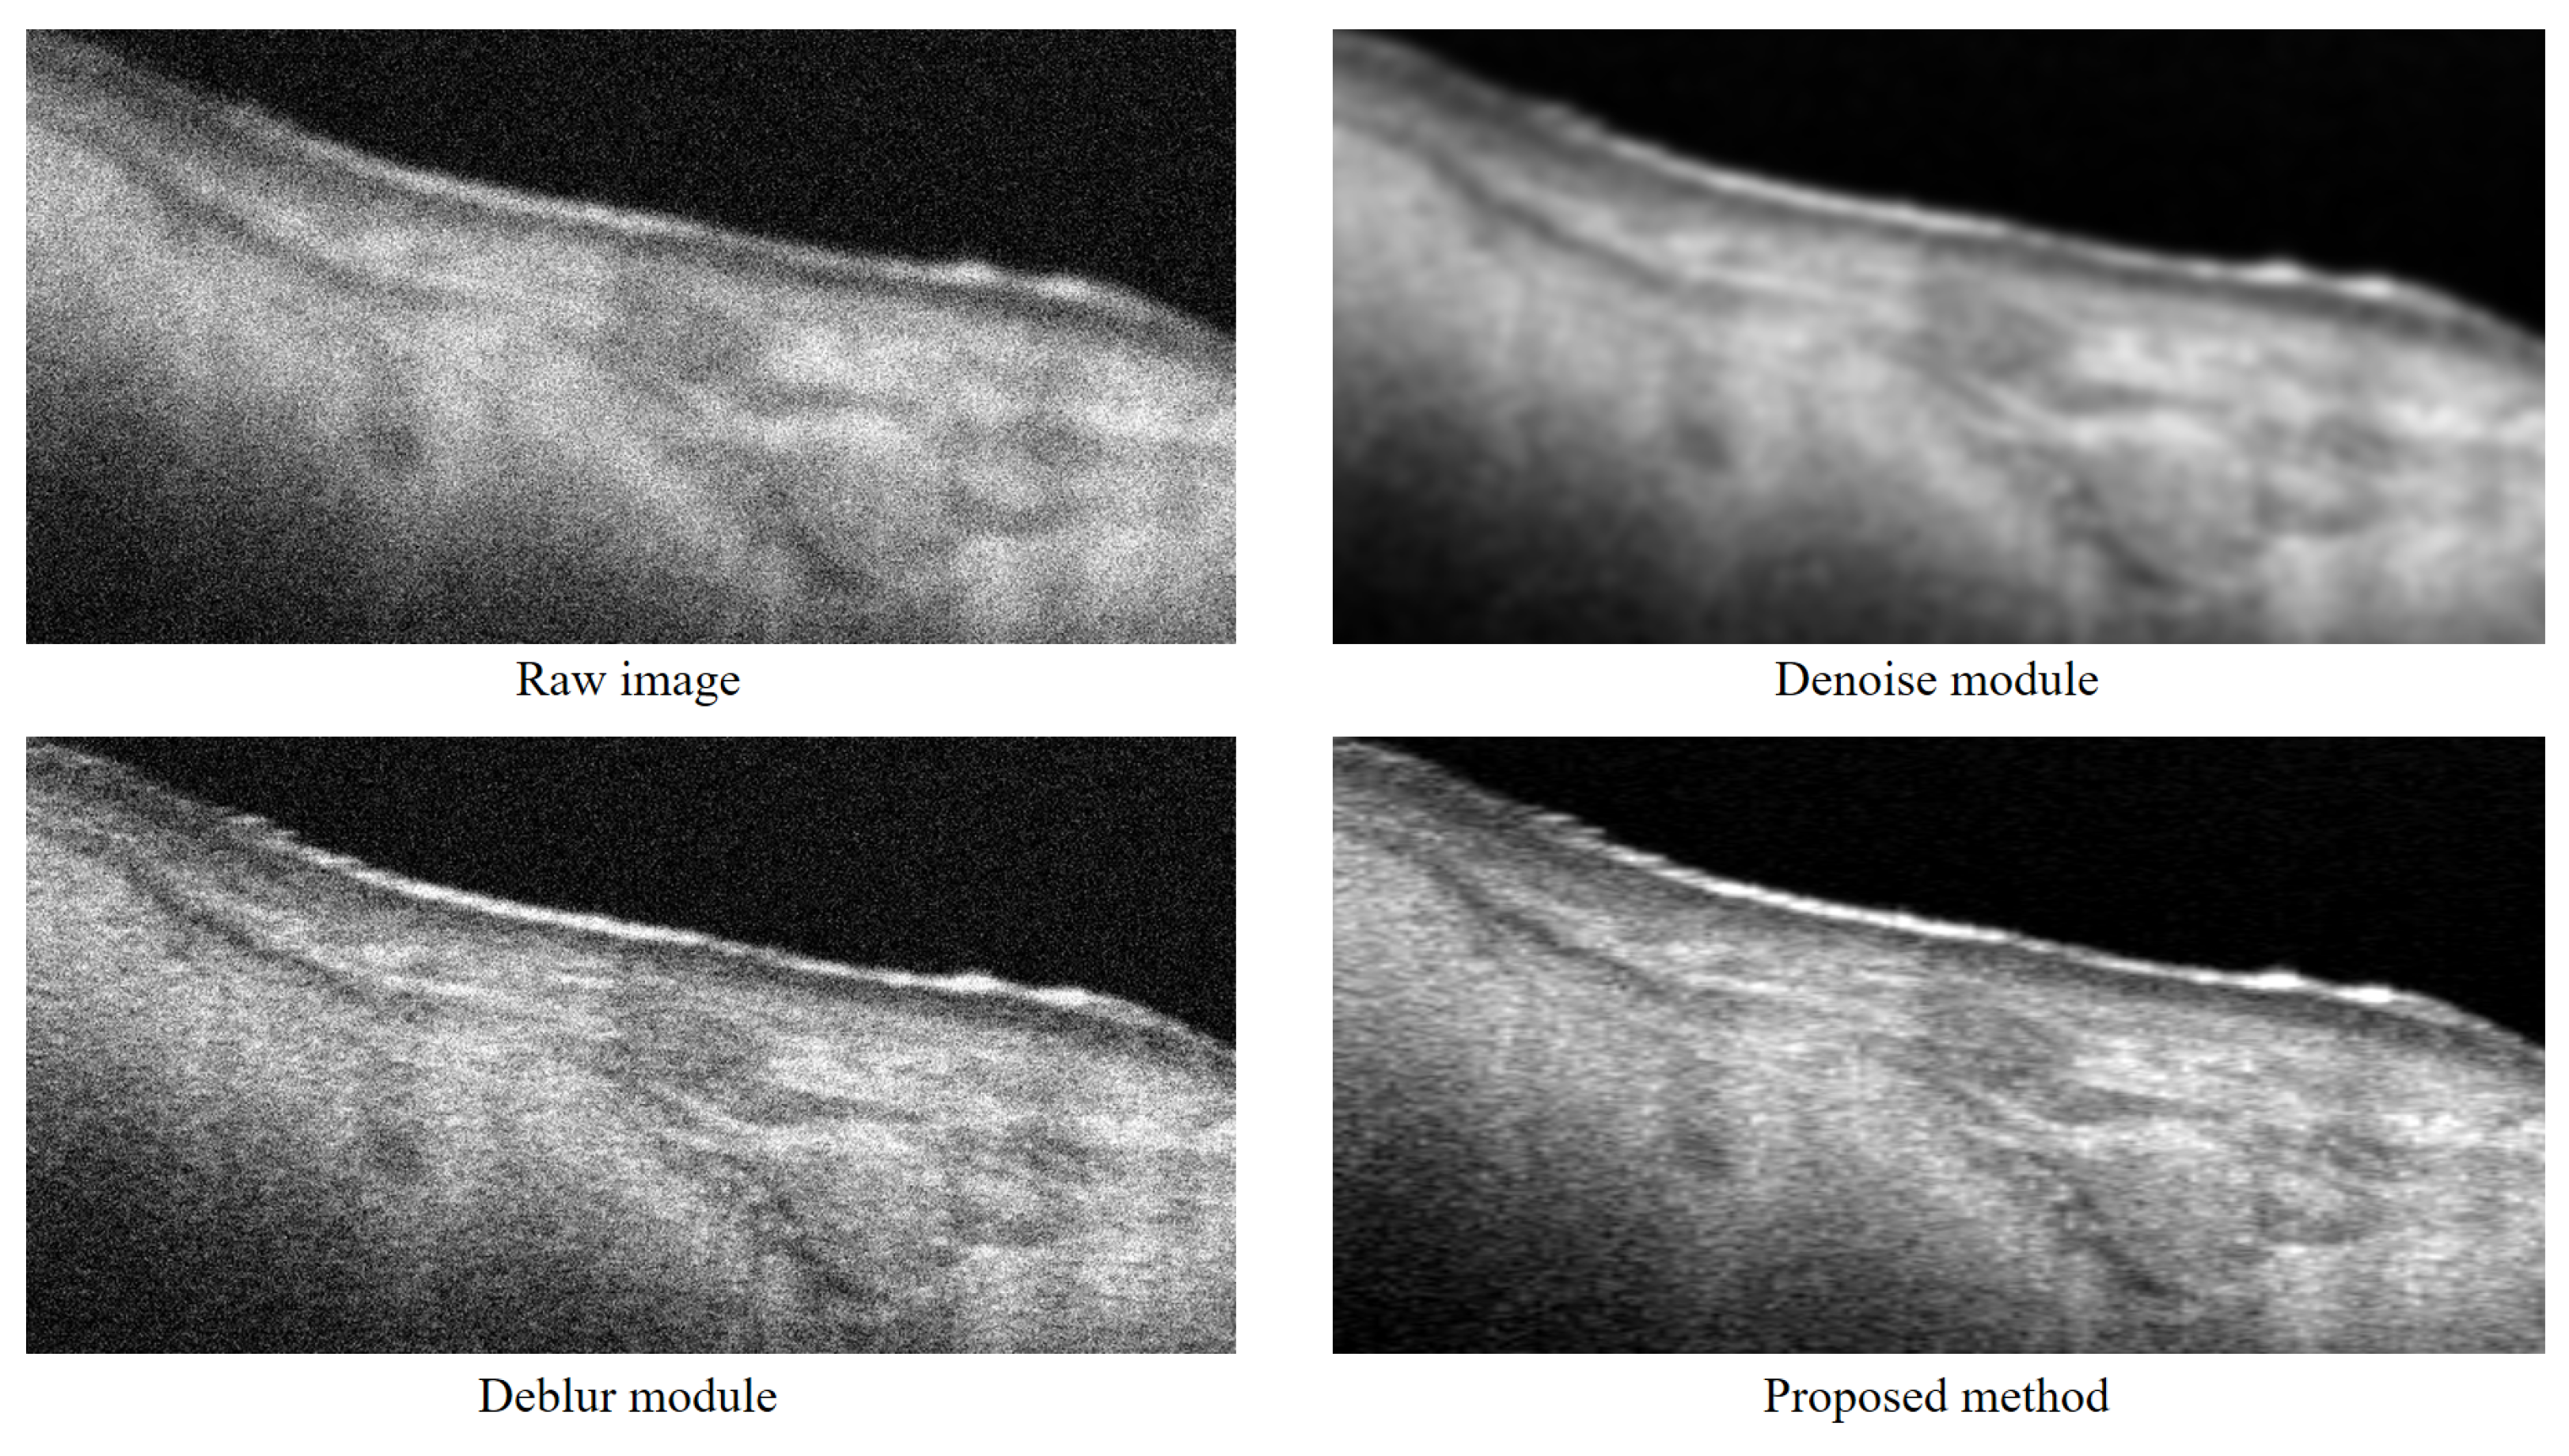

4.1. Ablation Study Results

| Original images | 8.94 ± 2.01 | 0.34 ± 0.14 |

| Denoise module | 19.53 ± 1.87 | 0.58 ± 0.20 |

| Deblur module | 17.55 ± 1.52 | 0.47 ± 0.12 |

| OSE | 26.71 ± 2.21 | 0.81 ± 0.16 |